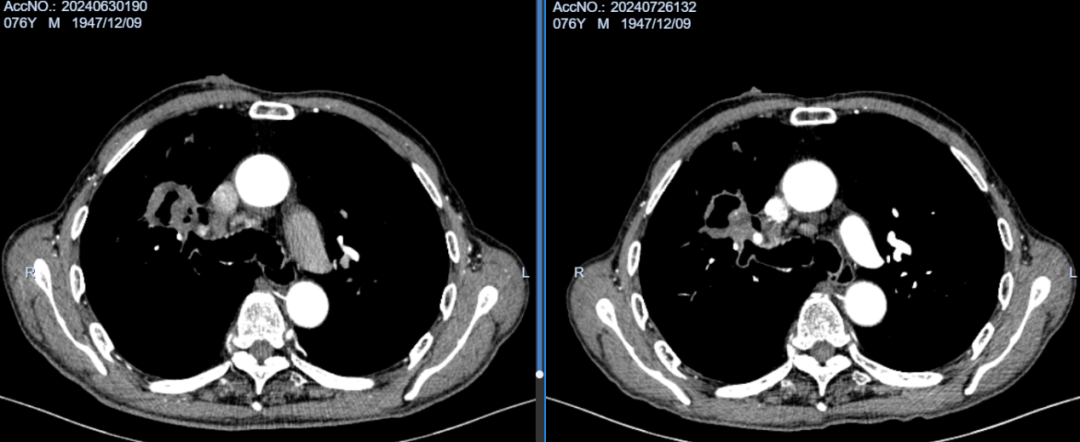

术后2月余,胸壁继发恶性肿瘤基本坏死,肺内原发病灶缩小明显,坏死空洞形成。

术后3月余,胸壁继发恶性肿瘤完全坏死,胸壁基本愈合,肺内病灶持续变小。